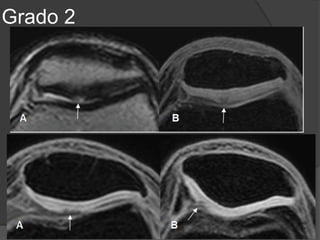

Grado II

• Roturas parciales

• Ligamento engrosado y áreas de hiperseñal en T1 y T2.

• Las fibras ligamentosas están separadas del hueso

cortical debido a la presencia de edema y hemorragia.